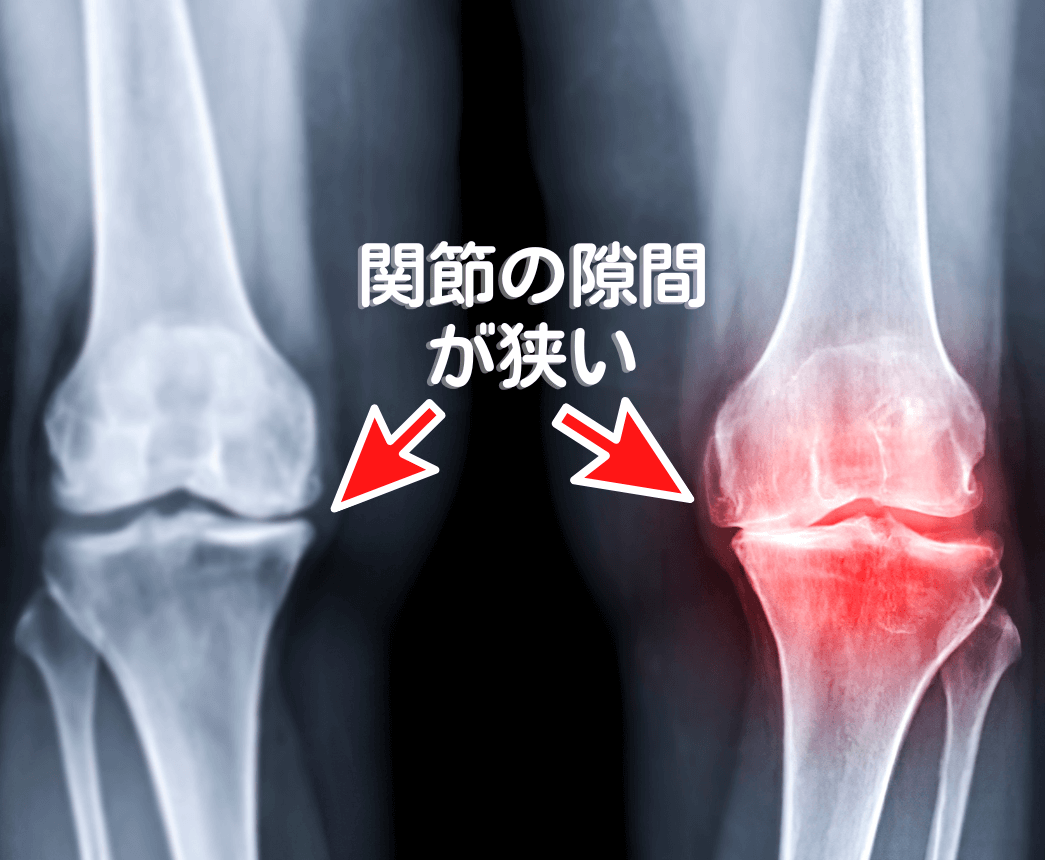

整形外科医は、画像診断のスペシャリストです。

レントゲンで

「骨が変形している」 「軟骨がすり減っている」

状態で原因が膝しかないと考えていれば、その結論は原因である膝自体を、

「人工関節に置き換える手術」の一択になります。

しかし、ここに大きな見落としがあります。

「レントゲンで変形や軟骨のすり減りが見られても、痛みがない人が多数存在する」

「変形の程度と、痛みの強さには相関関係がない」

そして、関節の動きはレントゲンには映りません。